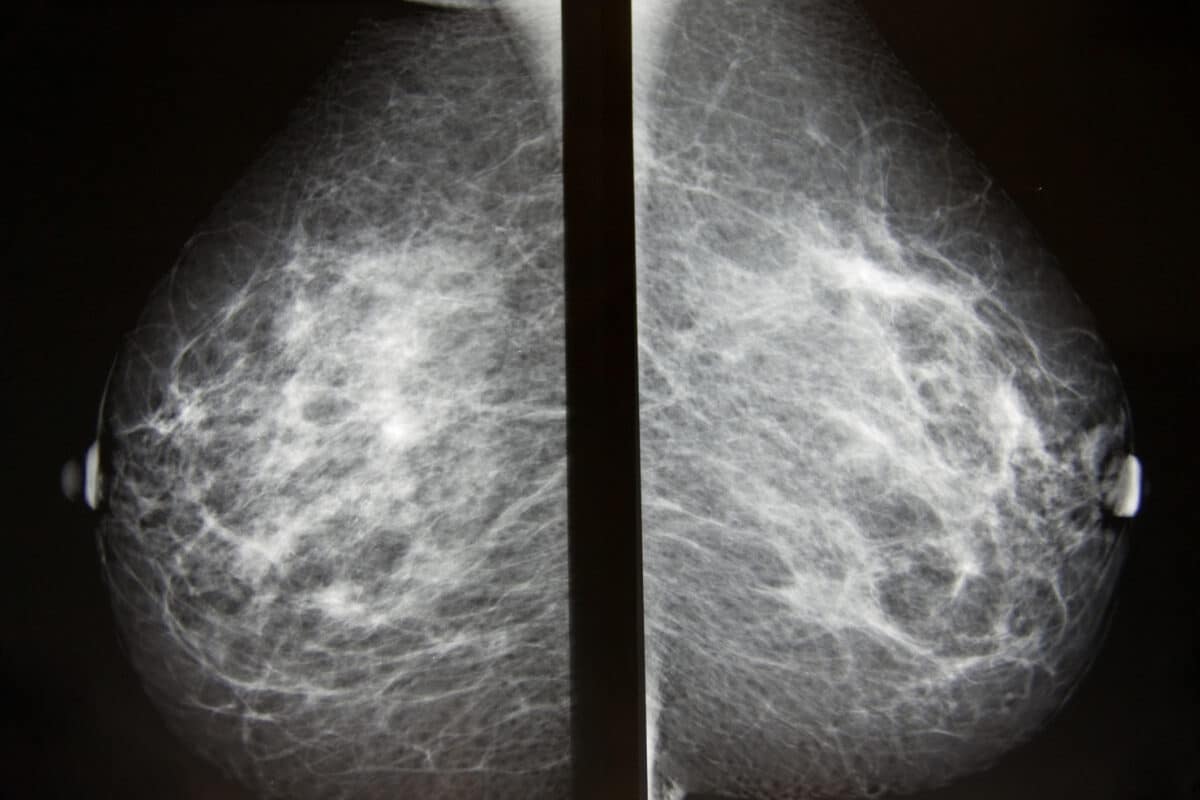

Un ensayo clínico comprueba que un suplemento diario de vitamina D durante la quimioterapia para el cáncer de mama eleva la tasa de desaparición completa del tumor del 24% al 43%

El estudio, liderado por Eduardo Carvalho-Pessoa de la Escuela de Medicina de Botucatu (UNESP, São Paulo), incluyó a 80 mujeres mayores de 45 años con cáncer de mama que iban a comenzar quimioterapia neoadyuvante (la que se administra antes de la cirugía para reducir el tumor). La mitad recibió 2.000 UI diarias de vitamina D3, la otra mitad, un placebo. Todas siguieron el mismo protocolo de quimioterapia.

Tras seis meses de tratamiento, la diferencia fue llamativa. En el grupo con vitamina D, el 43% de las pacientes experimentó una respuesta patológica completa: el tumor había desaparecido completamente. En el grupo placebo, solo el 24% alcanzó el mismo resultado. Hay que subrayar que 2.000 UI diarias es una dosis muy modesta (la corrección de una deficiencia severa de vitamina D requiere típicamente 50.000 UI por semana), lo que hace el hallazgo especialmente relevante desde el punto de vista de la seguridad y la accesibilidad económica.